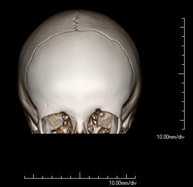

- Neurorradiología- TC Cráneo Prueba radiológica que consiste en obtener imágenes del cráneo de alta definición anatómica (tronco cerebral, cerebelo, cerebro, calota craneal, etc.), mediante el empleo de un equipo de TC (Tomografía Computarizada).Indicaciones: traumatismos, cefalea, trastornos de la memoria, pérdida de fuerza súbita en una extremidad o mitad del cuerpo. Prueba radiológica que consiste en obtener imágenes del cráneo de alta definición anatómica (tronco cerebral, cerebelo, cerebro, calota craneal, etc.), mediante el empleo de un equipo de TC (Tomografía Computarizada).Indicaciones: traumatismos, cefalea, trastornos de la memoria, pérdida de fuerza súbita en una extremidad o mitad del cuerpo.